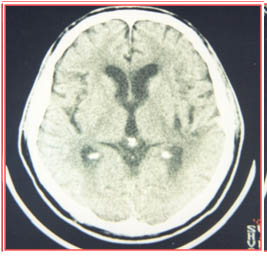

術(shù)后第10天